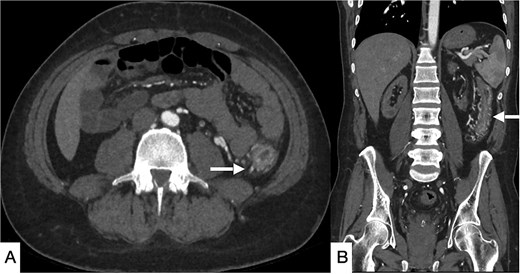

Three months later, the patient re-presented with severe right iliac fossa pain radiating to the left abdomen, associated with fever and clinical peritonism. Laboratory evaluation again demonstrated metabolic acidosis, leukocytosis, and elevated inflammatory markers. CT of the abdomen demonstrated pneumatosis intestinalis in the terminal ileum adjacent to the ileocolic anastomosis, together with new thrombi in the left common iliac and bilateral femoral veins (Fig. 3).

Contrast-enhanced CT of the abdomen and pelvis in axial (A–C), coronal (D), and sagittal (E, F) planes showing diffuse pneumatosis intestinalis just proximal to the previous anastomotic site (bold arrow), consistent with bowel ischemia. New thrombi are identified within the left common iliac vein (dashed arrow) and bilateral common femoral veins (arrowhead). Mild residual pneumobilia is present. An IVC filter is seen in situ.